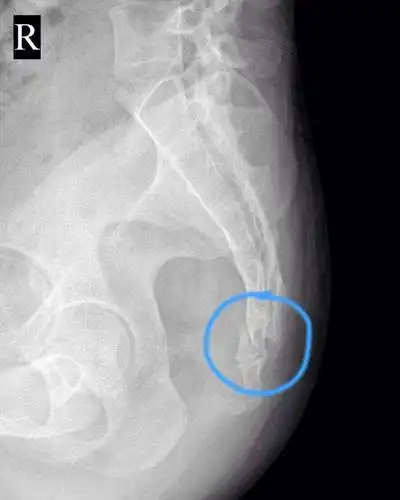

骶尾骨骨折后生小孩能顺产吗?如要不能还能正过来吗?